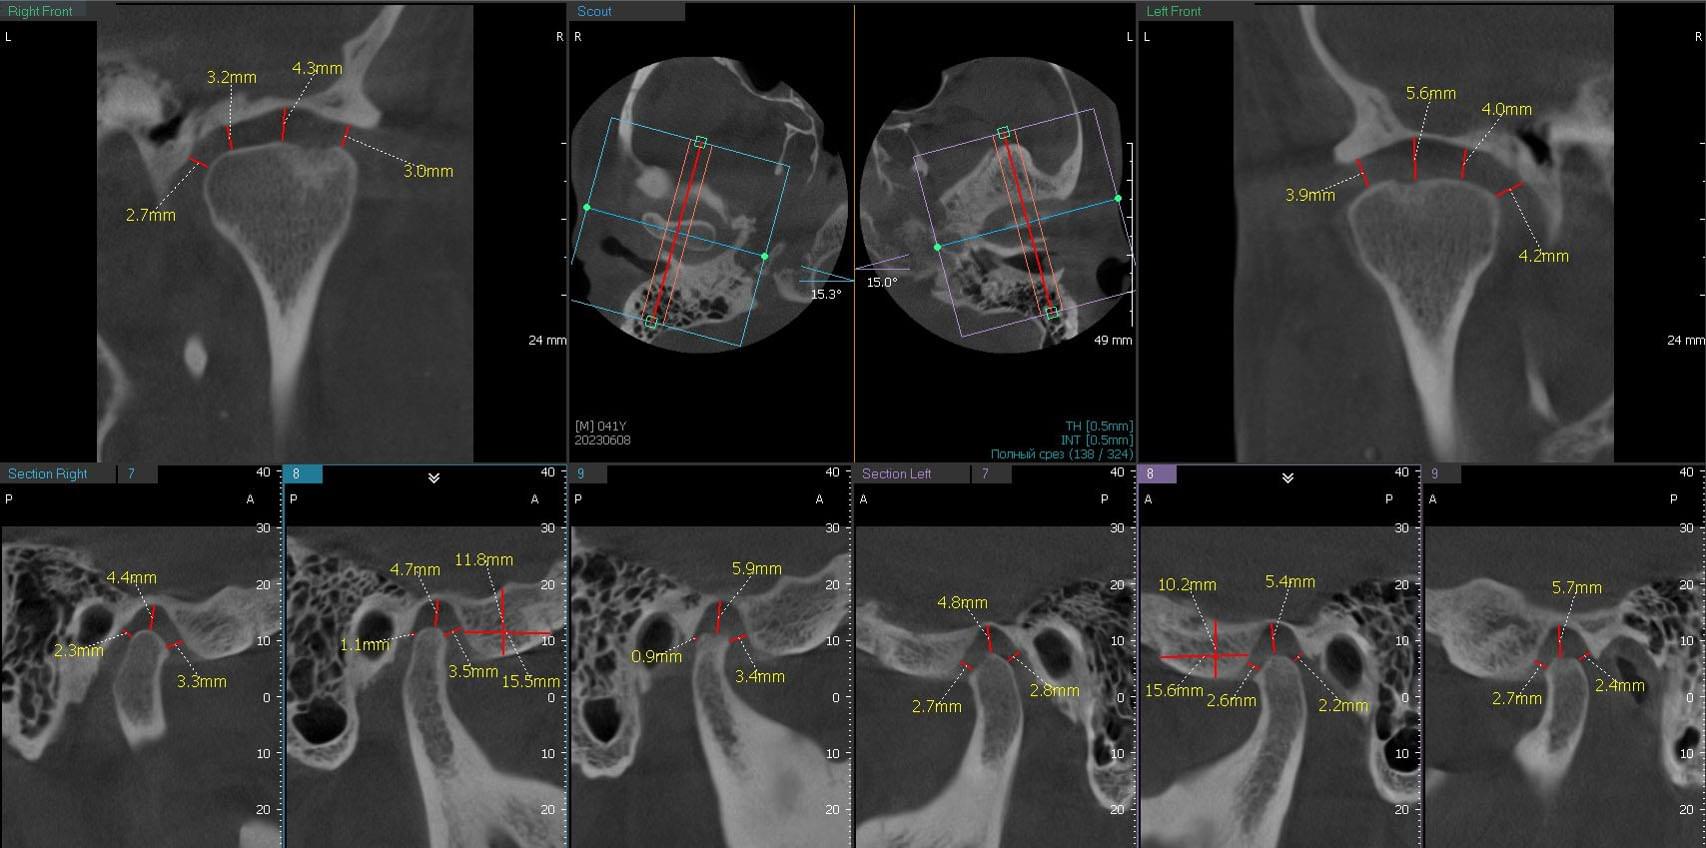

Pokud máte pochybnosti o svém temporomandibulárním kloubu, Myray Lab je tvoje spolehlivý Partner v diagnostice a identifikaci příčin této dysfunkce.Specializujeme se na provádění CT kloubů, lebek a okolních tkání, které nám umožňují podrobně vyhodnotit struktura a Funkce temporomandibulárního kloubu.

Jednou z hlavních výhod spolupráce s laboratoří je naše vysokoškolské vybavení, které Používá se v procesu CT.Používáme pokročilé technologie, které poskytují obraz vysoký vlastnosti a umožňují vám získat podrobné informace o stavu kloubu.Naše společnost Myray Lab použití inovativní metody a přístupy, které pomáhají našim klientům při přesné diagnóze a porozumění Problémy o jejich temporomandibulárním kloubu.

Zdraví našich zákazníků je naší prioritou, takže k každému nabízíme individuální přístup Pacient, který nás kontaktuje pro diagnostiku dysfunkce temporomandibulární kloubů.Náš Zkušení odborníci používají kombinaci klinické studie a CT skenování, aby to zjistili Příčiny příznaků a vyvinout účinný léčebný plán.